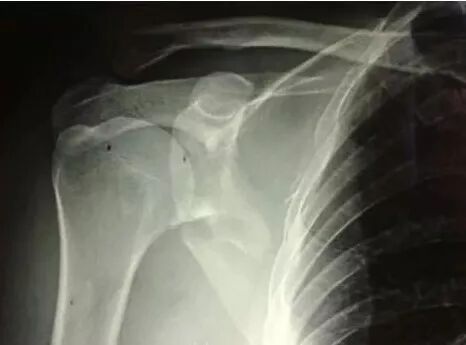

(2)肩胛带骨折

1)锁骨骨折

图片

骨折伤及锁骨下动脉,臂丛,应立即手术。

2)肩胛骨骨折

在2周之后手术,困难程度翻番。